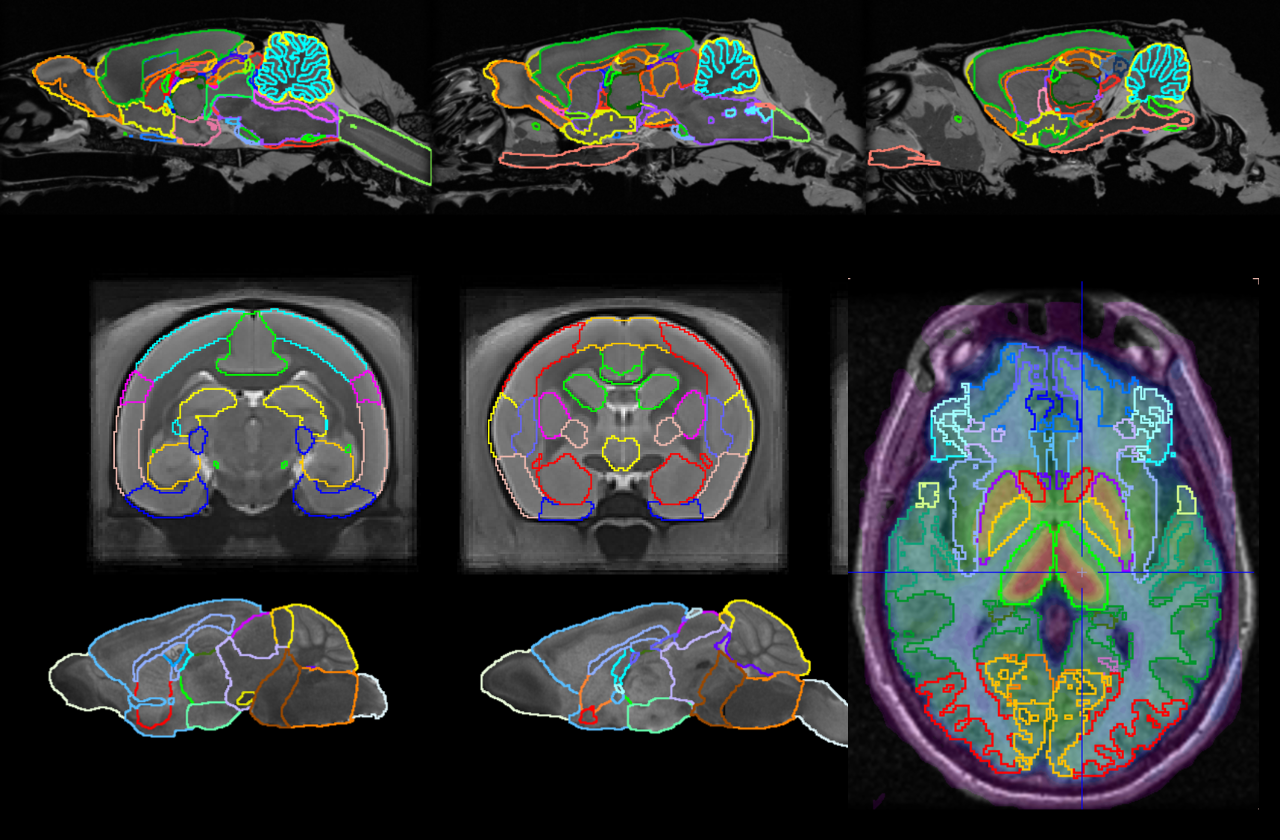

Workflow-based brain segmentation helps you extract the statistics you need for PET and PET/MR. User-expandable brain atlas resources help you customise for your research.

PNROD Rodent Brain Analysis

PNROD gives you brain segmentation workflows for small animal PET, PET/CT and PET/MR with the same direct access to statistics, kinetic modelling & parametric mapping.